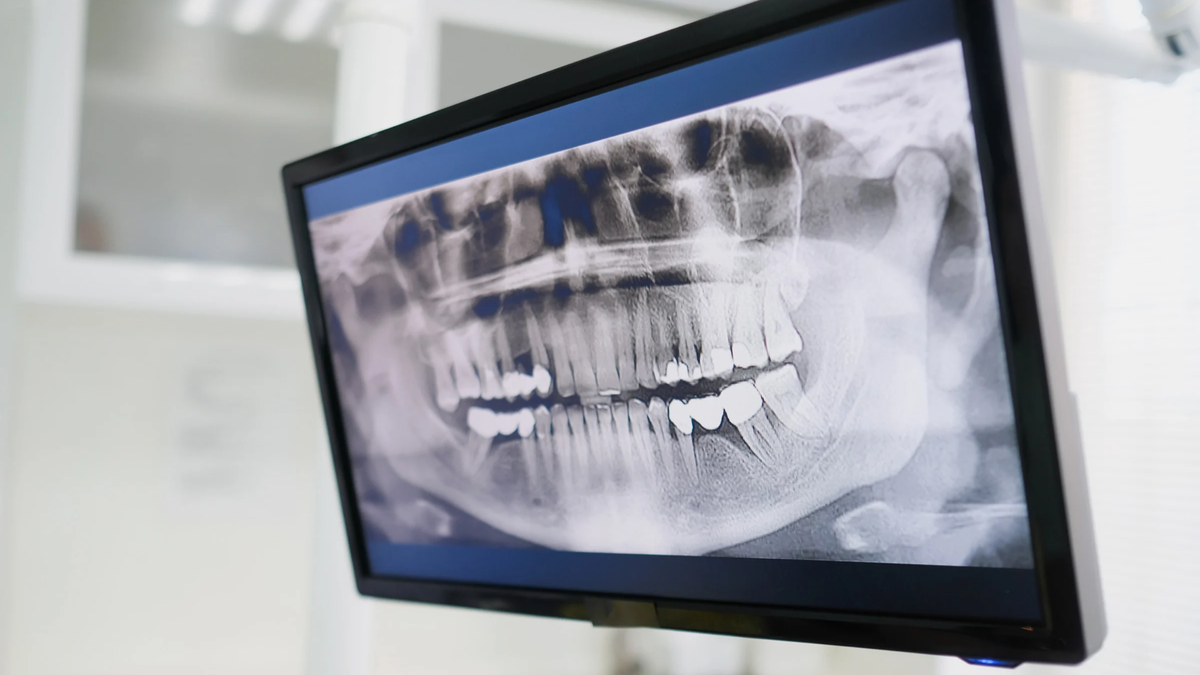

Рентгенологическое обследование-это быстрая и безболезненная процедура, обычно используемая для получения изображений внутренних костных структур, а в нашем случае и для визуализации корневых каналов.

Проходя через тело, энергия рентгеновских лучей поглощается с разной скоростью разными частями тела. Датчик на другой стороне тела улавливает рентгеновские лучи после того как они прошли и превращает их в изображение. Именно изображение снимка на компьютере и анализирует врач.

Плотные структуры и образования, через которые рентгеновским лучам труднее пройти, например кости, отображаются на изображении в виде четких белых областей. Мягкие части, через которые рентгеновские лучи могут легче проходить (десна, пульпа зуба и воспалительные очаги)-отображаются как более темные области.